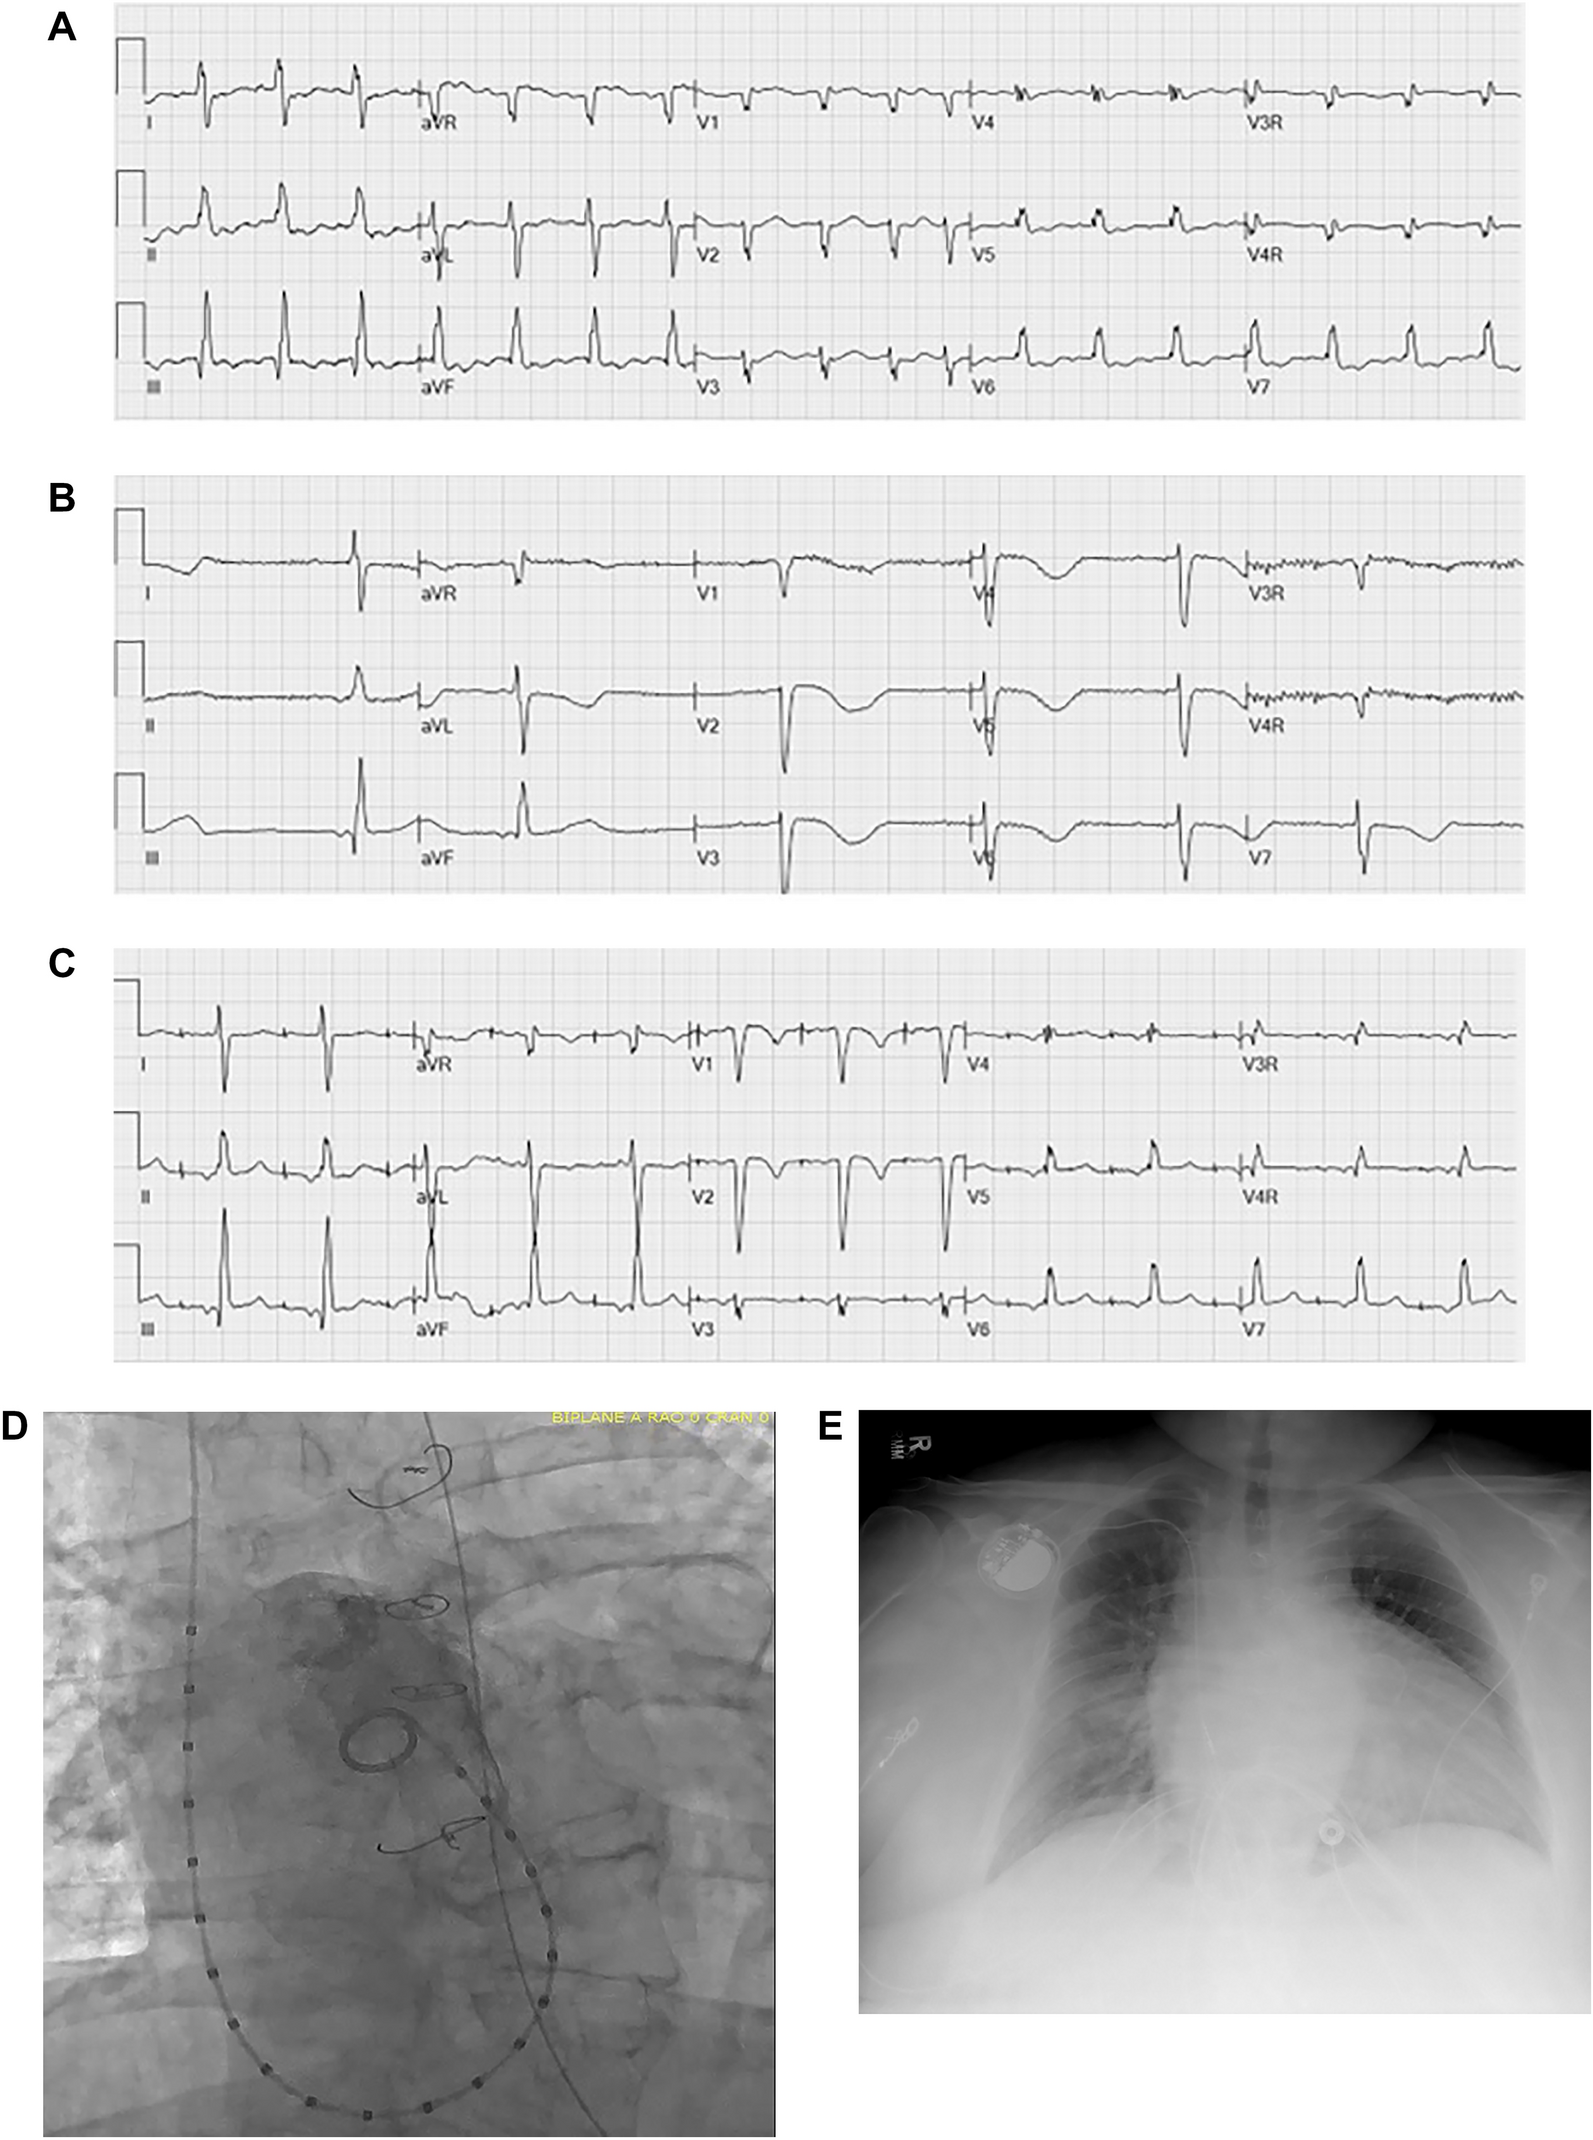

Fig. 6

Transvenous atrial lead for treatment of sinus node disease and atrial arrhythmias in a 36-year-old woman with tricuspid atresia and AP Fontan with numerous comorbidities. Ablation was considered a poor option due to likely prolonged anesthesia time and high likelihood of recurrence. Permanent single chamber pacemaker placed under conscious sedation with no complications allowed for atrial pacing and anti-arrhythmic therapy. a ECG demonstrating atrial tachyarrhythmia. b ECG demonstrating baseline sinus node disease with baseline rhythm ectopic atrial bradycardia, prohibiting use of anti-arrhythmic therapy. c ECG after placement of transvenous atrial lead with atrial pacing and intact AV conduction, allowing for addition of anti-arrhythmic medications. d Angiogram of a 36-year-old with AP Fontan, demonstrating size of dilated Fontan. e Transvenous atrial lead placed successfully in a 36-year-old woman with markedly dilated atriopulmonary Fontan and numerous comorbidities, not considered to be a candidate for Fontan conversion surgery